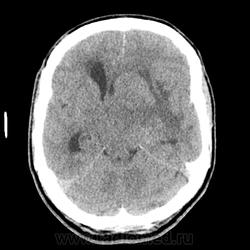

КТ ГМ+С Объемное образование левой гемисферы большого мозга. Внутрижелудочковая менингиома?

Мужчина 66 лет. Поступил с подозрением на ОНМК. Жалобы на атаксию и когнитивные нарушения (родственники рассказали о его плохой памяти, рассеянности, забывчивости, в последнее время, а также о нарушении речи и невнятности в произношении "мямлил"). Объемное образование в теменной, височной доли и базальных ядрах слева. Вазогенный отек. Выраженный масс-эффект. Латеральная дислокация вправо на 1,5см. Не могу дифференцировать интравентрикулярно ли, субэпендимарно ли расположено или за счет такого масс-эффекта? Ипсилатеральный желудочек компремирован, контрлатеральный компенсаторно расширен, височные рога боковых желудочков расширены, III желудочек значительно сужен и не дифференцируется, IVинтактен. Сильвиев водопровод сужен, достоверно не дифференцируется, супраселлярная цистерна сужена. Субарахноидальные борозды и конвекситальные пространства сужены. Выраженно диффузно очень интенсивно накапливает КВ. DDs: более вероятно: менингиома,  менее вероятно: субэпендимарная АСЦ, анапластическая АСЦ, глиобластома. Сложилось впечатление с большей вероятностью о внутрижелудочковой менингиоме с экстравентрикулярным ростом.

На нативе  до 45HU, после контрастирования плотность увеличилась до 60HU.